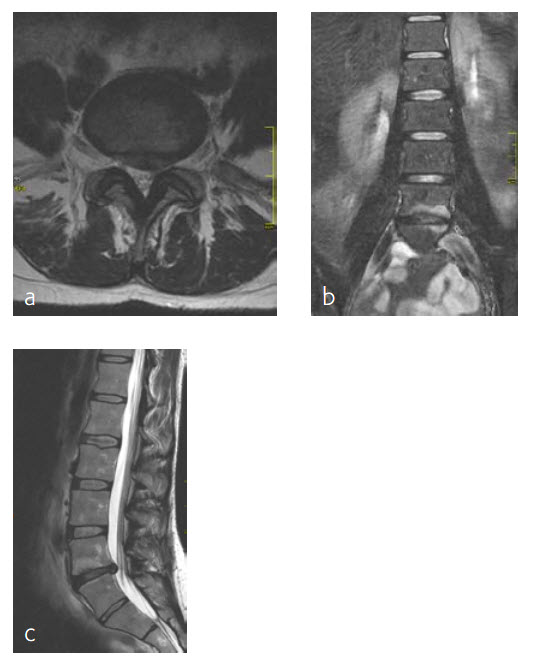

A 47-year-old woman was suffering chronic low back pain for several years, with severe pain attacks and with uncontrolled movements becoming increasingly disabling due to DD and erosive osteochondrosis at L4/L5. Condition after sciatica due to a disc herniation L4/L5, having nonoperative treatment. The MRI findings progressive compared to April 2014 are shown (Fig 5 and 6).